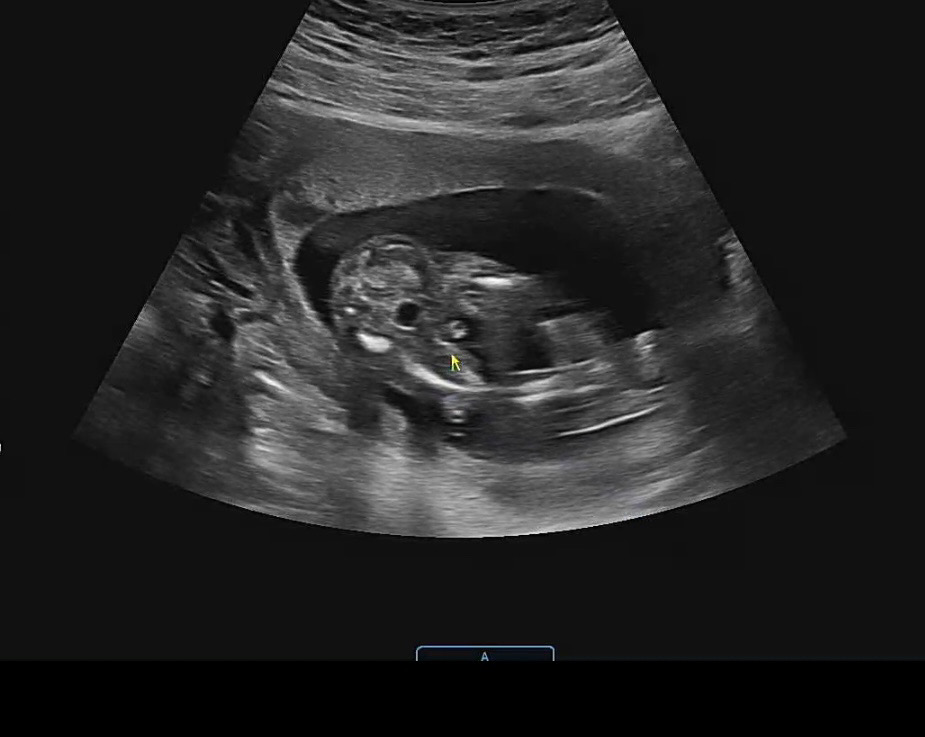

16주 성별 보고 왔어요! 확정이겠죠...?

의사쌤이 저기 뭐가 보이네요~ 정도로만 말씀해주셨는데 이건 이들 확정인거죠?!